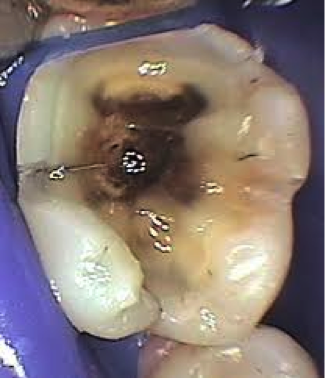

Το περιεχόμενο που κατ’ επανάληψιν εξέρχεται του στομάχου είναι όξινο και έχει ως αποτέλεσμα τη διάβρωση των δοντιών.

Η εξωτερική στιβάδα του δοντιού, η αδαμαντίνη (σμάλτο), προσβάλλεται, τα άλατά της διαλύονται, το δόντι αδυνατίζει “μαλακώνει’’ προοδευτικά και καταστρέφεται. Αυτό συμβαίνει σε πολλά δόντια με αποτέλεσμα εκτεταμένη βλάβη του στόματος.

Η διάβρωση των πίσω δοντιών, γομφίων και προγομφίων, μαζί με την αποτριβή που συνήθως συνυπάρχει έχει ως αποτέλεσμα την κατάρρευση της κάθετης διάστασης του προσώπου με αποτέλεσμα μία γερασμένη εμφάνιση.

Τα προσβεβλημένα δόντια ευκολότερα προσλαμβάνουν χρωστικές από τις τροφές, τα ποτά, το κάπνισμα με αποτέλεσμα άσχημη εμφάνιση.